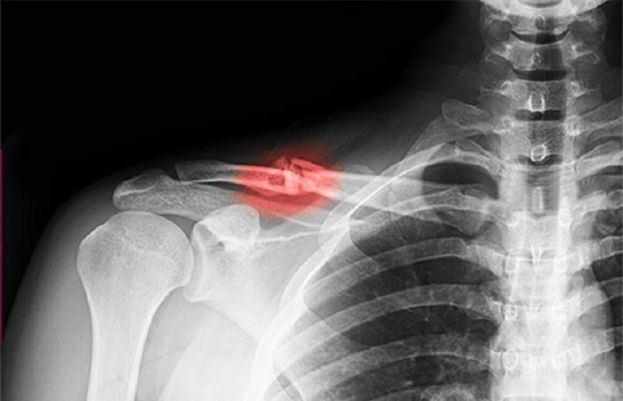

ہڈی کے بال یا سادہ فریکچر اپنے وقت پر ٹھیک ہوجاتے ہیں لیکن پیچیدہ فریکچرکے بعد ہڈی کی بحالی میں مہینے لگ جاتے ہیں۔

نیچر مٹیریلز میں شائع ہونے والی ایک تحقیق کے مطابق ایک بایومٹیریل پر اسٹیم سیل اور ہڈی کے خلیات کا لیپ کیا گیا اور جب اسے ٹوٹی پھوٹٰی ہڈی پر لگایا گیا تو اس سے ہڈیاں تیزی سے ٹھیک ہونے لگیں۔

اس طرح شدید حادثوں کے بعد ہڈی کے ٹھیک نہ ہونے والے زخم بھرے جاسکیں گے بلکہ انفیکشن کا خطرہ بھی ٹل جائے گا۔ اس میں ایک خاص قسم کے حیاتیاتی مادے (بایومٹیریل) کو پروٹین سے ڈھانپا گیا ۔ یہ پروٹین پورے جسم کی افزائش اور مرمت کے لئے استعمال ہوتا ہے۔

تجربات سے معلوم ہوا کہ یہ ہڈیوں کی قدرتی افزائش کو تیزترکردیتا ہے۔ اس موقع پر اسٹیم سیل (خلیاتِ ساق) بھی اہم کردار ادا کرتے ہیں اور یوں مرمتی عمل تیز ہوجاتا ہے۔ مریض کو دیر تک ہسپتال میں نہیں رکنا پڑے گا جبکہ بالخصوص بوڑھے لوگوں کو اس سے بہت فائدہ ہوگا۔

فی الحال ہڈیوں کی مرمت کے لئے مصنوعی پیوند یا عطیہ کندگان کی بافتیں (ٹشوز) لگائی جاتی ہے۔

اس عمل میں ٹوٹ پھوٹ کو ٹھیک کرنے کے لئے کسی دوسرے کی ہڈی کے خلیات لگانے پڑتے ہیں۔ یہ عمل کبھی کامیاب ہوتا ہے تو کبھی خاطر خواہ نتائج نہیں ملتے۔

اگرچہ خلیات سے ٹوٹی ہڈی کی بحالی کا تصور بہت پرانا ہے لیکن کئی صورتوں میں یا تو خلیات مرجاتے ہیں یا پھر طویل صحتیابی میں کوئی کردار ادا نہیں کرپاتے ۔

لیکن ہڈی نما پٹی لگانے سے پروٹٰین اور اضافی اسٹیم سیل پوری ہڈی میں سرایت کرجاتے ہیں اور یہ عمل تیز تر ہونے لگتا ہے۔

کنگز کالج میں ڈاکٹر شکری حبیب اور ان کے ساتھیوں نے یہ پٹی تیار کی ہے جو بطورِ خاص فریکچر پر عمل کرتے ہوئے صحتمند حصوں پر اثر نہیں ڈالتی۔ تجربہ گاہ میں آزمائش کے دوران اس ٹیکنالوجی نے صرف ایک ہفتے میں اسٹیم سیل کو ہڈی نما ٹشو میں بدل دیا۔

پھر اسے فریکچر والی جگہ پر لگایا گیا۔ فی الحال اسے بعض جانوروں پر آزمایا گیا ہے اور اگلے مرحلے میں انسانی آزمائش شروع ہوگی۔